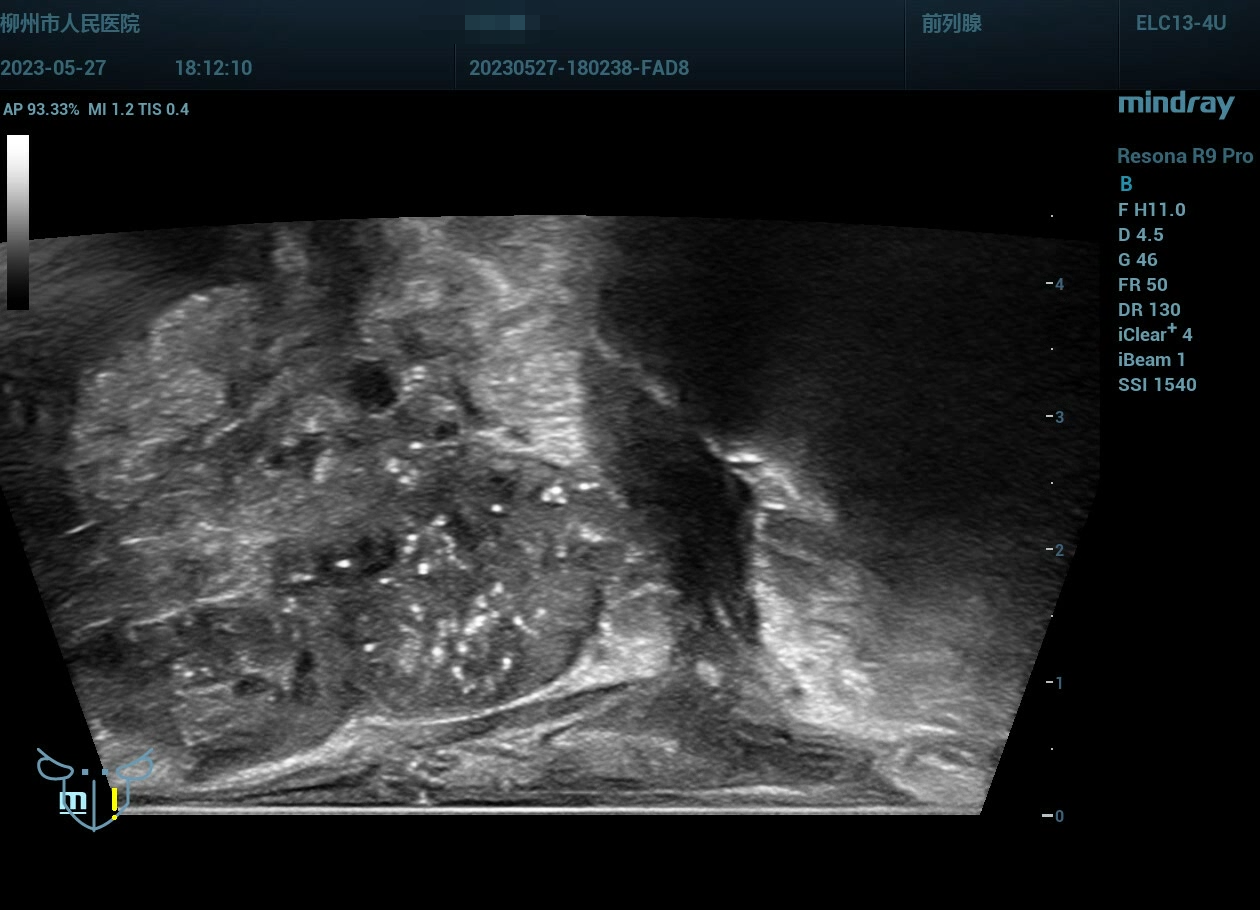

经会阴前列腺穿刺,病例实操(前列腺癌),柳州市人民医院,2023年

老年男性

经会阴前列腺穿刺,病例实操(前列腺癌),柳州市人民医院,2023年-主页丨今日超声